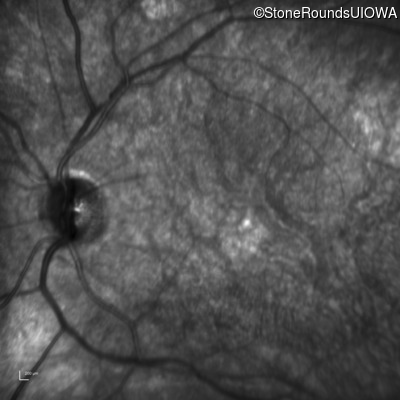

Infrared Fundus Photograph - Right - 20/125 -2

Exemplar